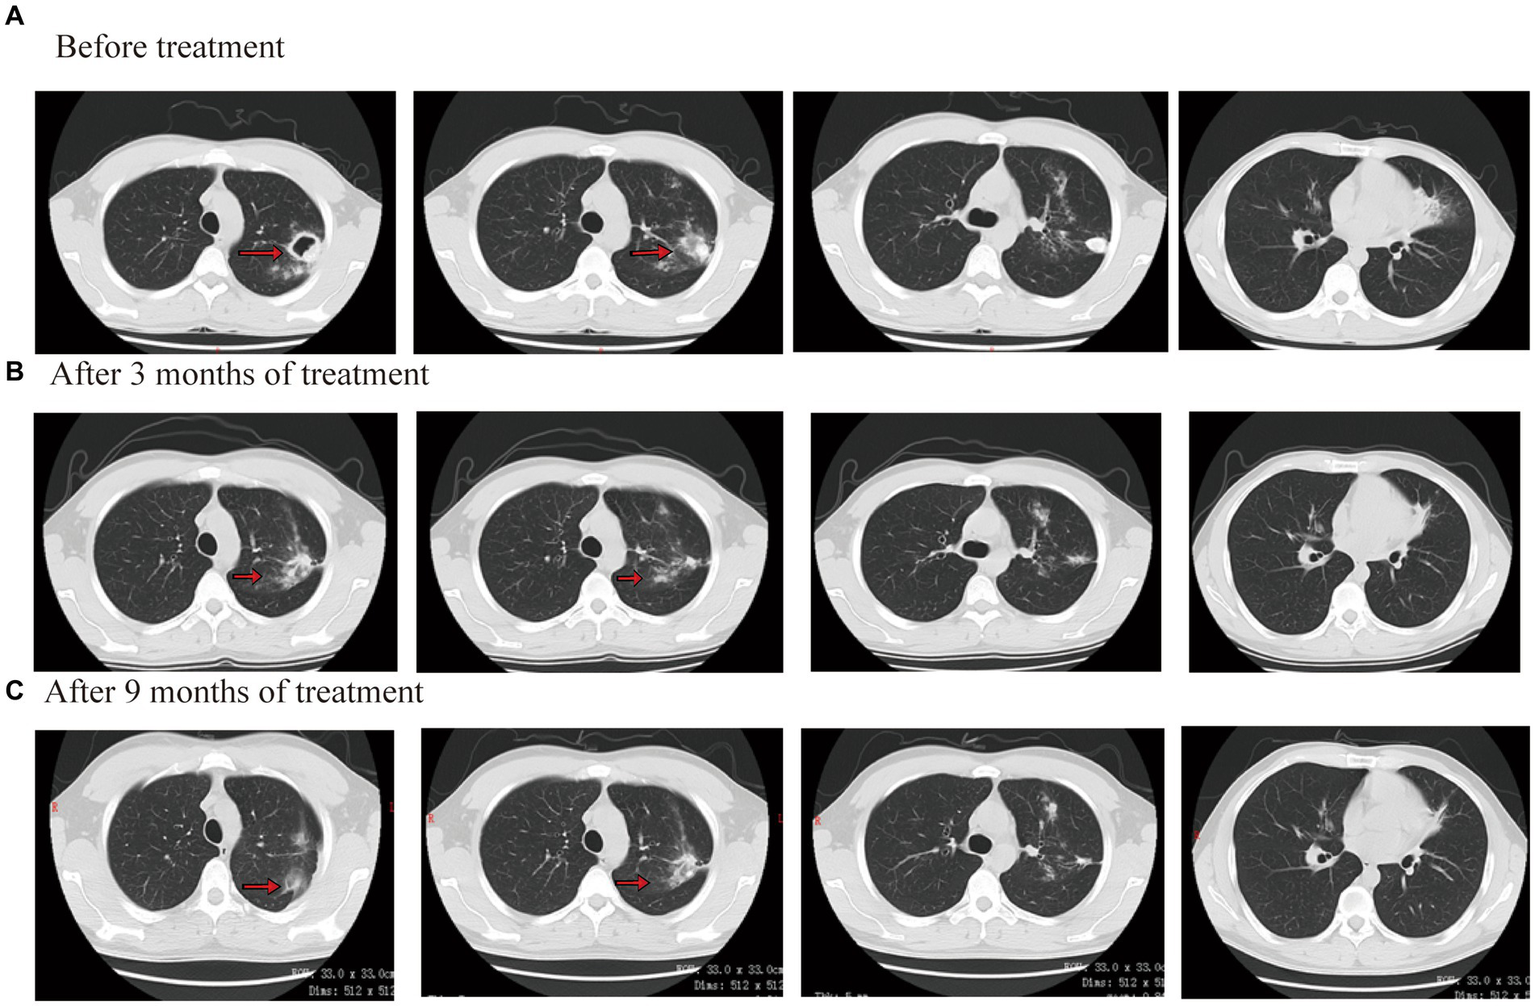

Figure 4

Chest CT scan images before and after treatment for case 3.

Considering that the patient underwent liver transplantation, some drugs were avoided as much as possible. The patient completed a cycloserine psychological assessment. Contezolid (400 mg/q12h, orally), cycloserine (0.25 g/bid, orally), levofloxacin (0.6 g/qd, orally), bedaquiline (400 mg/qd, orally), and clofazimine (100 mg/qd, orally) were given. Bedaquiline was changed to 200 mg/tiw after 2 weeks. The patient’s body temperature returned to normal, symptoms of cough and sputum improved, and numbness and pain in both lower limbs were relieved by approximately 70%. After 3 months of treatment outside the hospital, the lesions were clearly absorbed and improved. The CT scan showed that both lung consolidation shadows had been absorbed and the left lung cavity had closed (Figure 4B). In November 2021, the result of the Mycobacterium sputum culture was negative. The WBC was 4.56 × 109/L with a neutrophil ratio of 75.5%, HGB was 116 g/L, and PLT was 138 × 109/L. Bedaquiline was discontinued after 6 months and continued to be treated with contezolid, cycloserine, levofloxacin, and clofazimine. After 3 months of treatment, the patient’s body temperature was normal, there was no obvious cough or sputum, and the numbness and pain in both lower limbs were relieved. In March 2022, the result of the Mycobacterium sputum culture was negative. In June 2022, CT showed that both lung diseases were smaller than before (Figure 4C). The administration process is shown in Figure 2C.